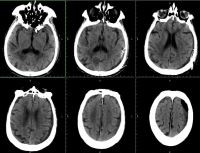

高血压脑出血【详细】